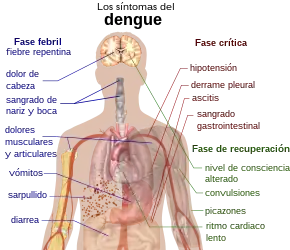

Cuadro clínico

El cuadro clínico de la fiebre dengue y la presentación de las diversas manifestaciones y complicaciones, varía de un paciente a otro. Típicamente, los individuos infectados por el virus del dengue son asintomáticos (80 %). Después de un período de incubación de entre cuatro y diez días, aparece un cuadro viral caracterizado por fiebre de más de 38 °C, dolores de cabeza, dolor retroocular y dolor intenso en las articulaciones (artralgia) y músculos (mialgia) ―por eso se le ha llamado «fiebre rompehuesos»―, inflamación de los ganglios linfáticos y erupciones en la piel puntiformes de color rojo brillante, llamada petequia, que suelen aparecer en las extremidades inferiores y el tórax de los pacientes, desde donde se extiende para abarcar la mayor parte del cuerpo.[15][39]

La enfermedad ―a pesar de ser una sola―[43] tiene dos formas de presentación: dengue y dengue grave. Después de un periodo de incubación de 2 a 8 días, en el que puede parecer un cuadro catarral sin fiebre, la forma típica se expresa con los síntomas anteriormente mencionados. Hasta en el 80 % de los casos la enfermedad puede ser asintomática o leve, incluso pasando desapercibida. La historia natural de la enfermedad describe típicamente tres fases clínicas: Una fase febril, que tiene una duración de 2 a 7 días, una fase crítica, donde aparecen los signos de alarma de la enfermedad (dolor abdominal, vómito, sangrado de mucosas, alteración del estado de conciencia), trombocitopenia, las manifestaciones de daño de órgano (hepatopatías, miocarditis, encefalopatía, etc.), el choque por extravasación de plasma o el sangrado severo (normalmente asociado a hemorragias de vías digestivas). Finalmente, está la fase de recuperación, en la cual hay una elevación del recuento plaquetario y de linfocitos, estabilización hemodinámica, entre otros.[44]